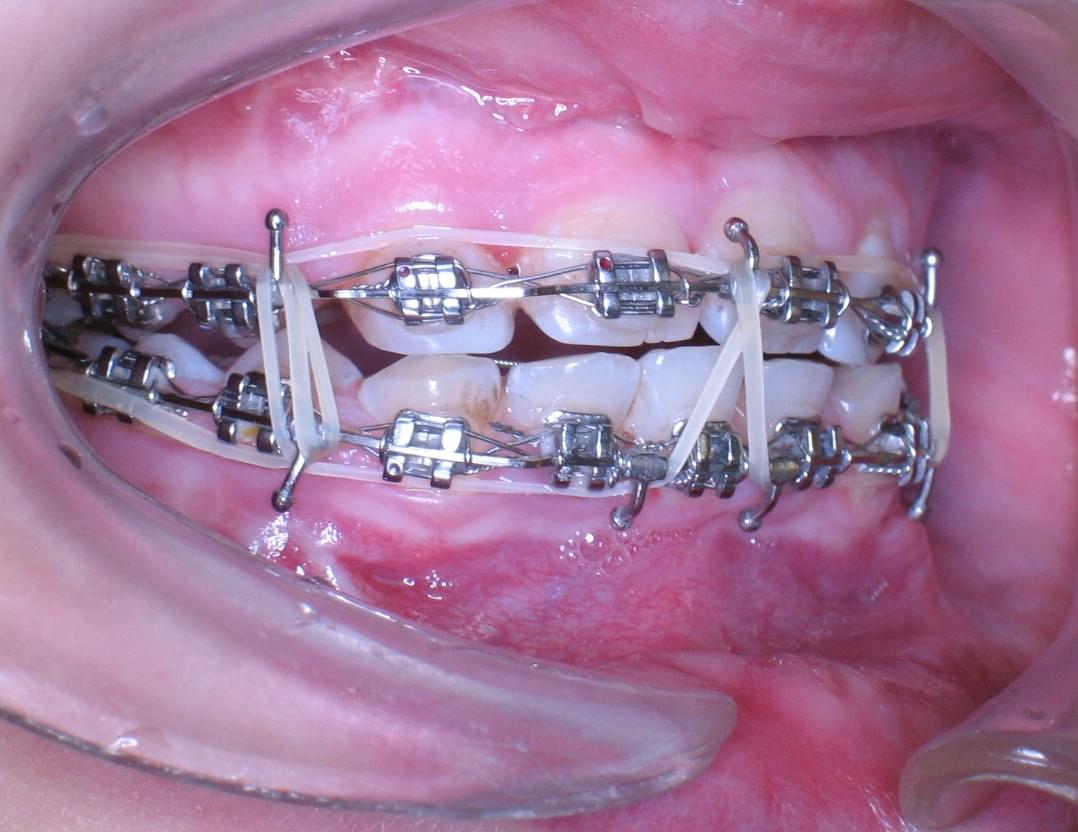

Po dokončení růstu v roce 2012 jsem mohla absolvovat jednu z náročných stomatochirurgických operací a to ortognátní operaci spodní i horní čelisti. Jedná se o jejich posun. Poté měla následovat implantace všech zubů, ta se však kvůli vysokým finančním nákladů nemohla uskutečnit.

Od té chvíle mi na zubech zůstaly fixační rovnátka, která drží všechny zuby při sobě se snahou udržet je v čelisti, co nejdéle to půjde a zabránit vypadnutí.

Potřebuji tedy náročnou implantaci všech zubů, nejen kvůli normálnímu příjmu potravy, ale i kvůli stabilizaci čelistních kloubních hlavic a nastavení správného skusu čelistí.